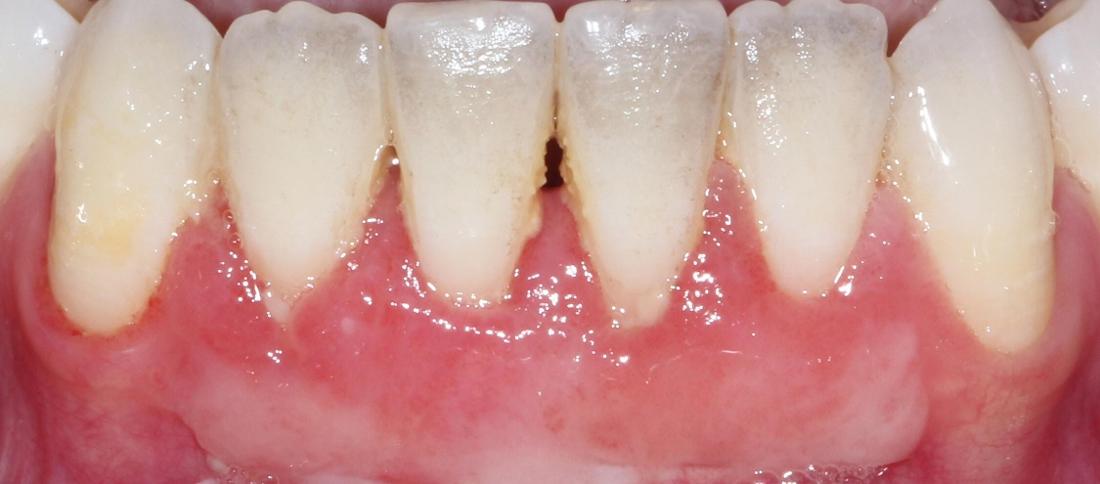

Before: Patient reports gum recession #25 and irritation when brushing